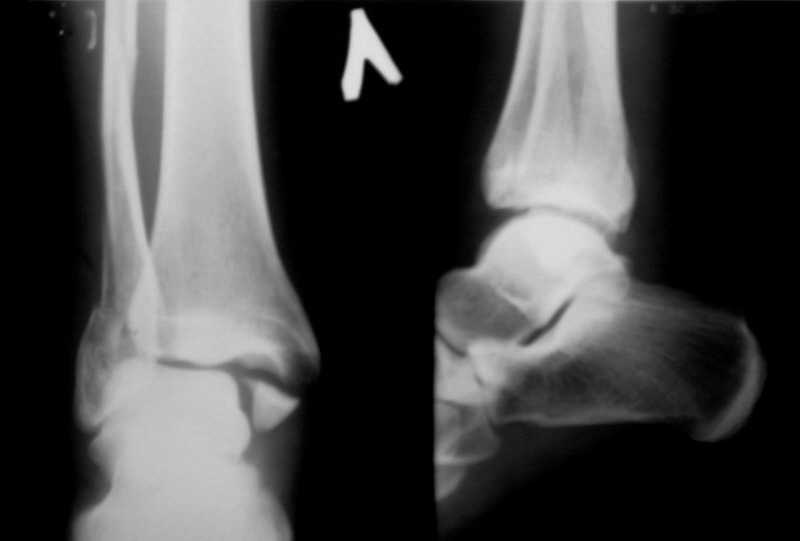

Перелом лодыжекКонтрольные рентгенограмы сделаны с нарушением укладок для стандартных проекций. Переделайте рентгенснимки и догда можно будет о чем-то иметь дискуcсию.

Рентгенограммы не сделаны в строго боковой и передне-задней проекциях.

Но и здесь видно, что внутренняя лодыжка "висит" - это говорит об интерпозиции. Выполняйте открытую репозицию и металлостеосинтез.

Можно сделать прямую с внутренней ротацией в 20 гр - еще лучше будет видно. Внутренняя лодыжка на боковом снимке не так уж плохо стоит. В любом случае - надо сделать нормальные снимки.

Вот рентгенконтроль на 7-е сутки после репозиции.

Стандартными снимками считается прямая, боковая и мортиз!!!, а так трудно гадать, насколько потеря длины малоберцовой. На боковом снимке не сопоставленный перелом медиальной лодыжки и перелом заднего края без смещения.